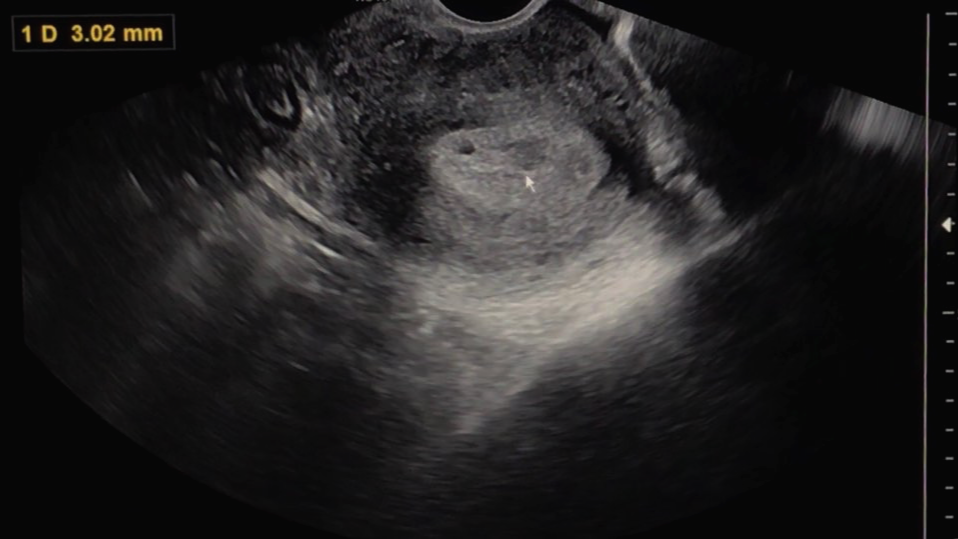

그리고 선생님은 초음파를 보면서 어떤 상태인지 한번 자세히 보자고 말씀하셨습니다.

아직은 확실하게 '아기집이 이거다!' 하고 보이지는 않는 상태이지만 와이프의 몸 안에 무언가가 생기기는 했나 봅니다.

확실히 아기집이 생겼다고 말씀을 안 해주시는 걸 보면 원장님 또한 아직은 조심스러운 상태이신 게 맞는 것 같습니다.

선생님은 문제가 없다면 10일 정도 후에는 아기집에서 아기의 심장이 뛰기 시작할 것이고, 14일 정도 후에 병원을 다시 한번 찾아오라고 하십니다. 그렇게 또다시 2주간 또 긴 기다림의 시간이 시작되는 것 같습니다.